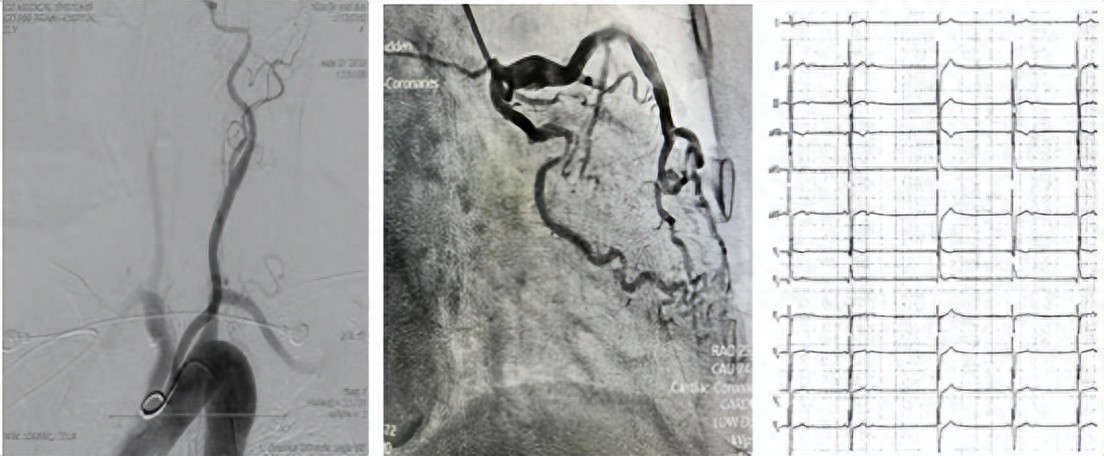

入院后一系列检查结果令人揪心:心电图提示窦性心律伴有 ST 改变,心脏彩超和胸部 CT 发现心脏扩大,脑血管造影显示脑血管轻度狭窄,而冠脉造影更是发现回旋支重度狭窄!

在检查过程中,郑全主任和廖家盛主任凭借丰富的经验,敏锐捕捉到多导联电生理检查仪中的异常 —— 存在严重的缓慢性心律失常!随后,蒋奶奶被迅速转入心血管内科病区。面对复杂病情,医院神经内科、心血管内科、介入中心专家立即开展 MDT(多学科诊疗)讨论。

经过严谨分析,最终为蒋奶奶制定了个性化治疗方案:先植入永久双腔抗核磁起搏器,解决心脏跳动过慢的问题,再进行标准化的冠心病、心力衰竭 GDMT(指南指导的药物治疗),从多个方面控制病情。

另一边,88 岁的王奶奶同样被心慌困扰了整整两年,四处求医却始终找不到病因,这次住院终于揪出了罪魁祸首 ——“心房颤动”。

就在同一天,安居区人民医院专家团队为她成功实施了 “经导管心脏射频消融术”,通过微创的方式,精准 “消灭” 异常的心脏电信号,让王奶奶的心脏重新恢复正常跳动节奏。